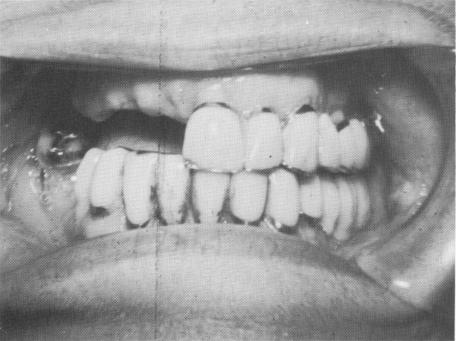

Fig. 4-23. The patient prior to implantation.

1 Clinical view prior to Chercheve endosseous spiral-post implantation